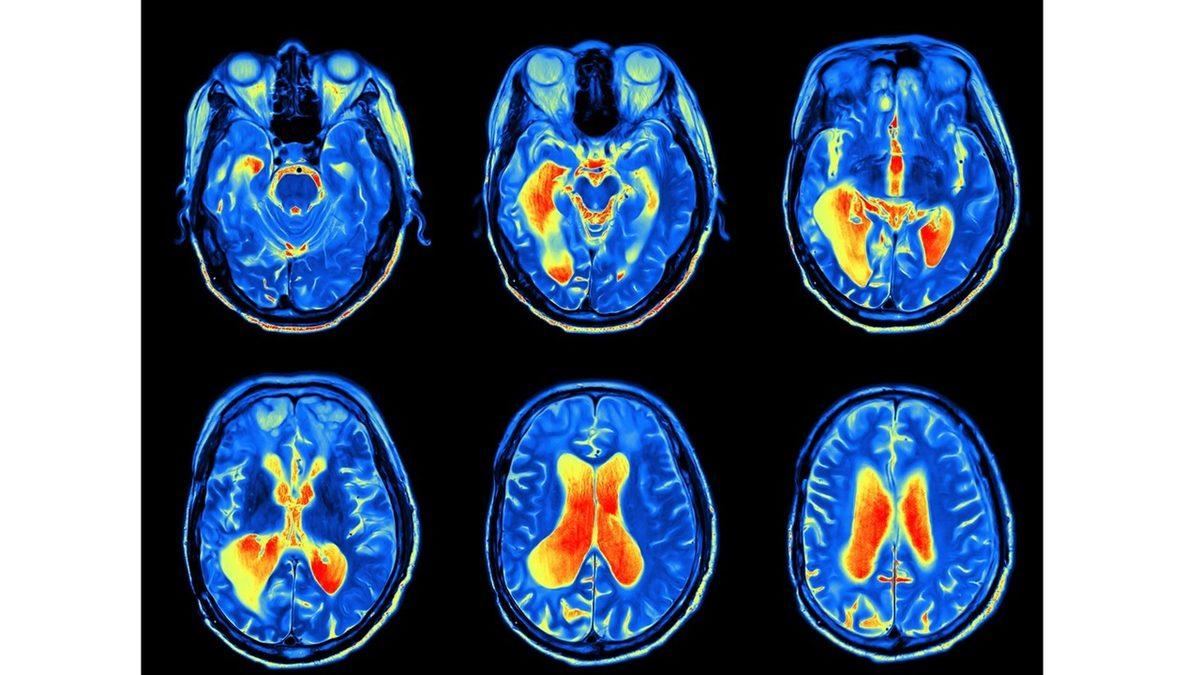

Beynin aktivitesini okumak için PET, EEG, fMRI gibi çeşitli beyin görüntüleme cihazları bulunmaktadır. Bir fMRI makinesine sahip bilişsel psikologlar, bir kişinin depresif düşüncelere sahip olup olmadığını söyleyebiliyorlar. Bunun yanında bir öğrencinin beyin kalıplarını öğretmenininkilerle karşılaştırarak hangi kavramlarda iyi olduğunu da görebiliyorlar.